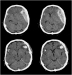

Evidenzbasierte Neurotraumatologie Journal für Neurologie, Neurochirurgie und Psychiatrie 2008; 9 (3): 20-27 Volltext (PDF) Summary Praxisrelevanz Abbildungen Keywords: Neurochirurgie, Neurotraumatologie Evidenzbasierte Medizin bedeutet die individuelle klinische Erfahrung mit der besten verfügbaren Evidenz aus systematischer Forschung zu vereinbaren. In der Neurotraumatologie lassen sich in der Akutphase kaum prospektive randomisierte Studien durchführen. Während der Behandlung von Patienten mit Schädelhirntrauma (SHT) kommt es immer wieder zu alltäglichen Fragestellungen, wie Zeitpunkt des Beginns der Thromboseprophylaxe, antikonvulsive Prophylaxe, Indikation und Art der Hirndruckmessung, Häufigkeit zerebraler CT-Kontrollen, auf die wir uns wissenschaftlich fundierte Antworten wünschen. Ziel dieser Arbeit war es, evidenzbasierte Antworten auf diese Fragen zu finden. Die zu den einzelnen Fragestellungen publizierten Studien wurden in prospektiv-randomisierte, retrospektive Studien und Fallberichte unterteilt. Dementsprechend ließ sich eine Therapierichtlinie bezogen auf spezifische Fragestellungen herausarbeiten. Bei fehlender wissenschaftlicher Grundlage wurden Therapieempfehlungen ausgearbeitet und in einigen Fällen ließ sich nur auf Expertenmeinungen hinweisen. |